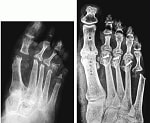

固定術・形成術

関節形成術

腱の形成術